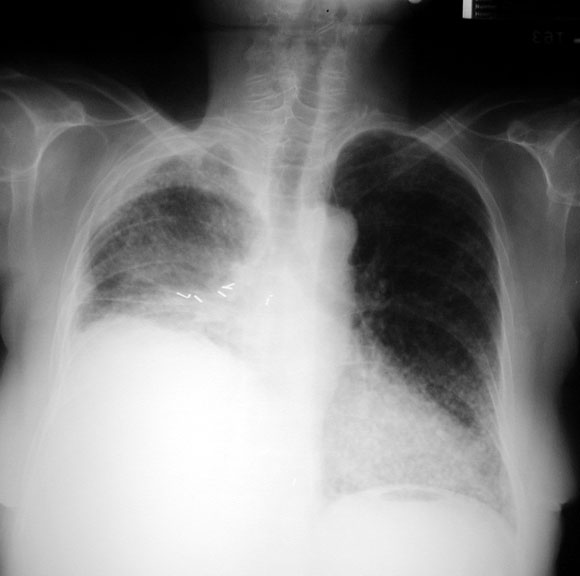

• Onset of diaphragmatic paralysis

Diaphragmatic paralysis